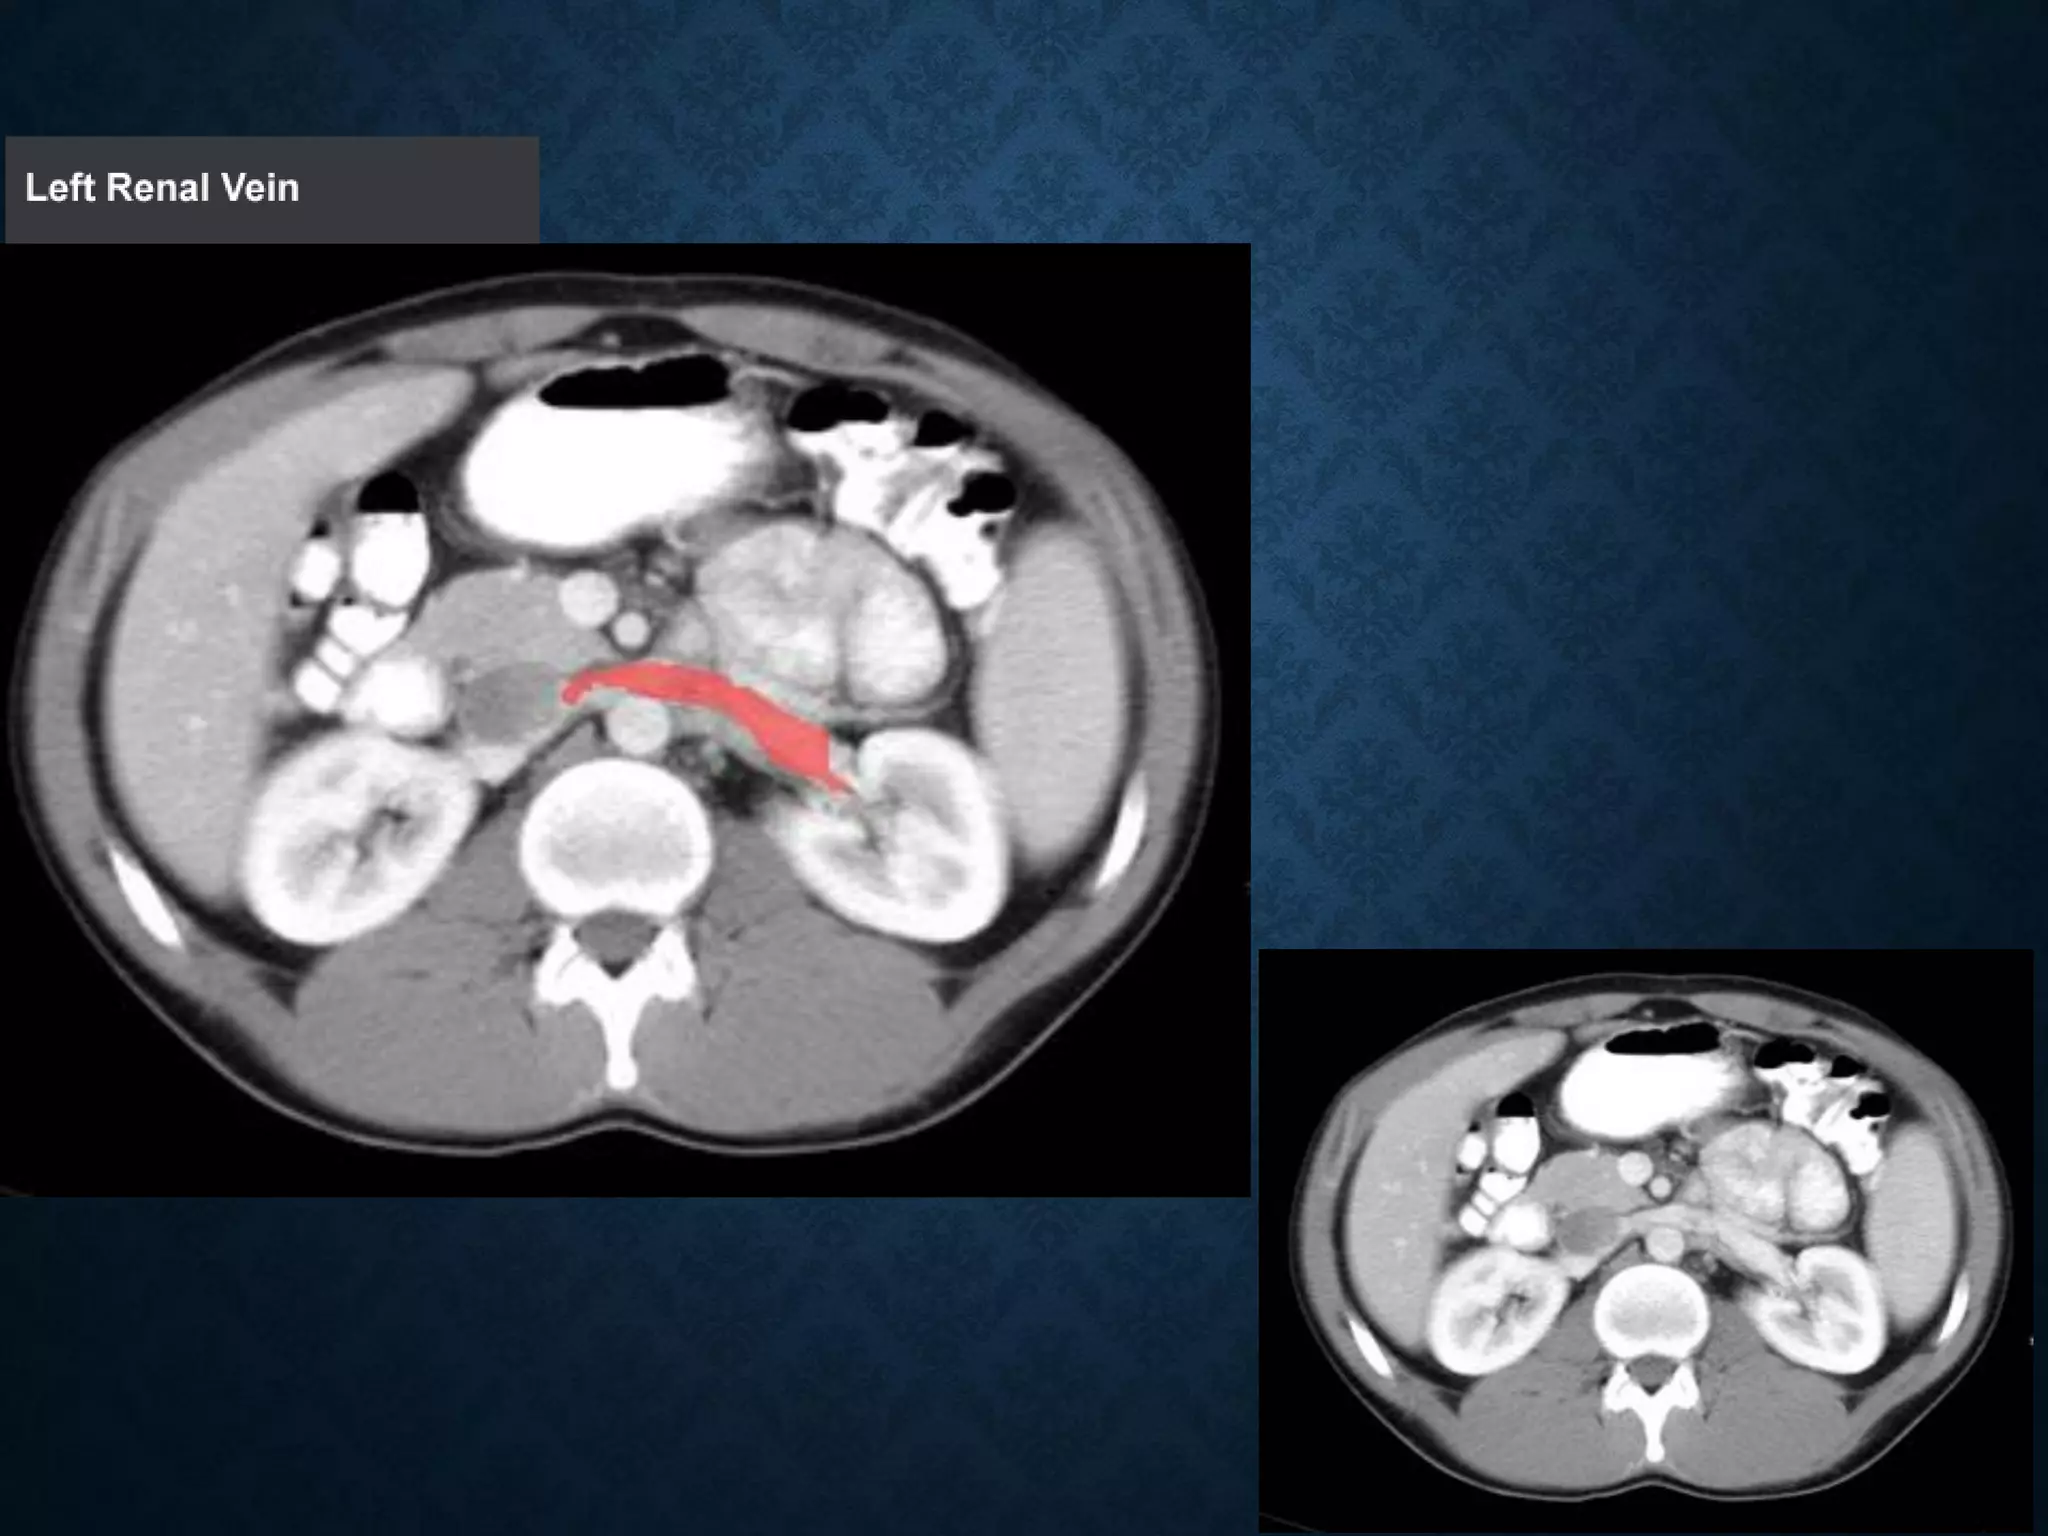

Identify the following structures in the body CT to the right. To view the location of the structure in the image click on

the label at the left and the structure will be indicated in the image. Abdominal CT scans typically begin just above

the diaphragm, so the first slice you see is of the lower chest.